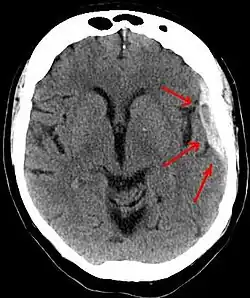

A person must receive medical assessment, including a complete neurological examination, after any head trauma. A CT scan or MRI scan will usually detect significant subdural hematomas.

Subdural hematomas occur most often around the tops and sides of the frontal and parietal lobes.[3][2] They also occur in the posterior cranial fossa, and near the falx cerebri and tentorium cerebelli.[3] Unlike epidural hematomas, which cannot expand past the sutures of the skull, subdural hematomas can expand along the inside of the skull, creating a concave shape that follows the curve of the brain, stopping only at dural reflections like the tentorium cerebelli and falx cerebri.

On a CT scan, subdural hematomas are classically crescent-shaped, with a concave surface away from the skull. However, they can have a convex appearance, especially in the early stages of bleeding. This may cause difficulty in distinguishing between subdural and epidural hemorrhages. A more reliable indicator of subdural hemorrhage is its involvement of a larger portion of the cerebral hemisphere. Subdural blood can also be seen as a layering density along the tentorium cerebelli. This can be a chronic, stable process, since the feeding system is low-pressure. In such cases, subtle signs of bleeding—such as effacement of sulci or medial displacement of the junction between gray matter and white matter—may be apparent.

Fresh subdural bleeding is hyperdense, but becomes more hypodense over time due to dissolution of cellular elements. After 3–14 days, the bleeding becomes isodense with brain tissue and may therefore be missed.[20] Subsequently, it will become more hypodense than brain tissue.[21]